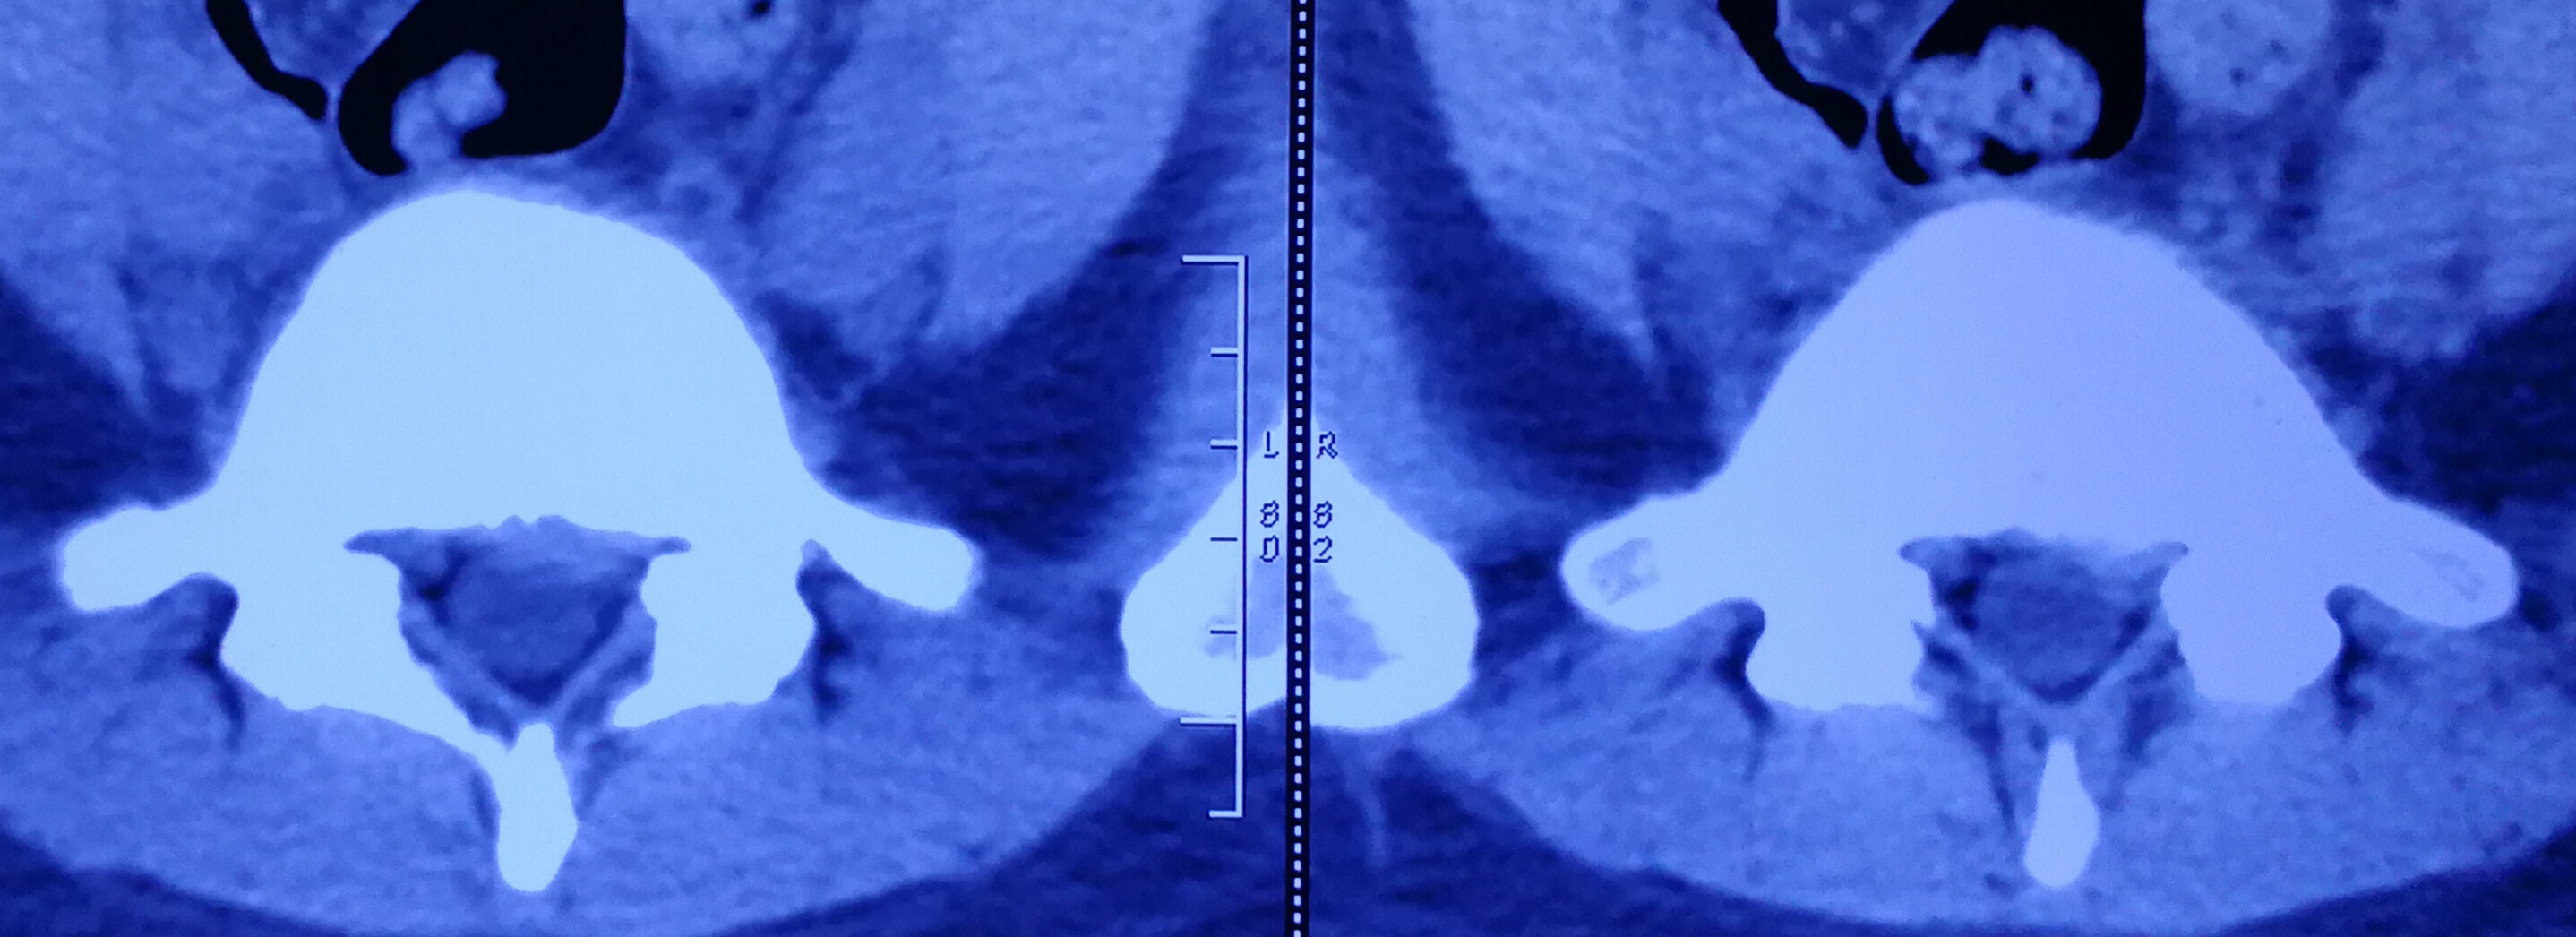

从磁共振片子上看,突出间隙位于腰4、5和腰5骶1,以腰5骶1间隙的椎间盘突出尤为明显,属于左后方的巨大突出,腰5神经根明显被挤压,已经看不清神经的走向,但右侧的神经根影子十分清楚,出现患肢的麻木也就是理所当然的了。目前体检发现左下肢直腿抬高试验40度阳性,加强试验阳性,右侧均为阴性,左侧小腿后外侧及足背外侧也有片状皮肤感觉减退区域,左侧跟腱反射微微有些减弱,右侧是正常的,看得出,骶1神经根是受到了一定的伤害。